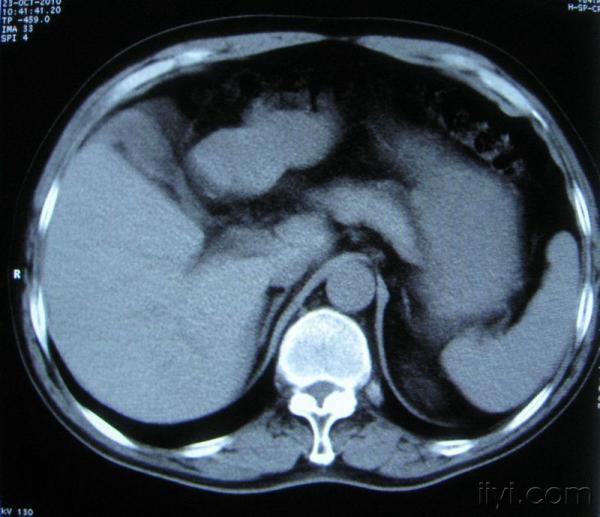

男。60岁,胸片示支气管炎治疗后复查CT。

你指那个肯定是淋巴结,中央系坏死,这很常见,特别在双侧腹股沟会经常看到。这个双侧腋窝及纵隔见多发小淋巴结征。

根据位置考虑应该是淋巴结,密度不均,是因为肿大的淋巴结中心液化坏死